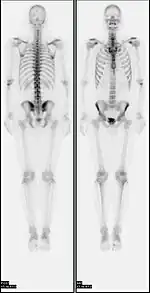

![]() A nuclear medicine whole-body bone scan. The nuclear medicine whole-body bone scan is generally used in evaluations of various bone-related pathology, such as for bone pain, stress fracture, nonmalignant bone lesions, bone infections, or the spread of cancer to the bone. | |

A bone scan or bone scintigraphy /sɪnˈtɪɡrəfi/ is a nuclear medicine imaging technique of the bone. It can help diagnose a number of bone conditions, including cancer of the bone or metastasis, location of bone inflammation and fractures (that may not be visible in traditional X-ray images), and bone infection (osteomyelitis).[1]

In a typical bone scan technique, the patient is injected (usually into a vein in the arm or hand, occasionally the foot) with up to 740 MBq of technetium-99m-MDP and then scanned with a gamma camera, which captures planar anterior and posterior or single photon emission computed tomography (SPECT) images.[19][14] In order to view small lesions SPECT imaging technique may be preferred over planar scintigraphy.[20]

In a single phase protocol (skeletal imaging alone), which will primarily highlight osteoblasts, images are usually acquired 2–5 hours after the injection (after four hours 50–60% of the activity will be fixed to bones).[19][14][21] A two or three phase protocol utilises additional scans at different points after the injection to obtain additional diagnostic information. A dynamic (i.e. multiple acquired frames) study immediately after the injection captures perfusion information.[21][22] A second phase "blood pool" image following the perfusion (if carried out in a three phase technique) can help to diagnose inflammatory conditions or problems of blood supply.[23]